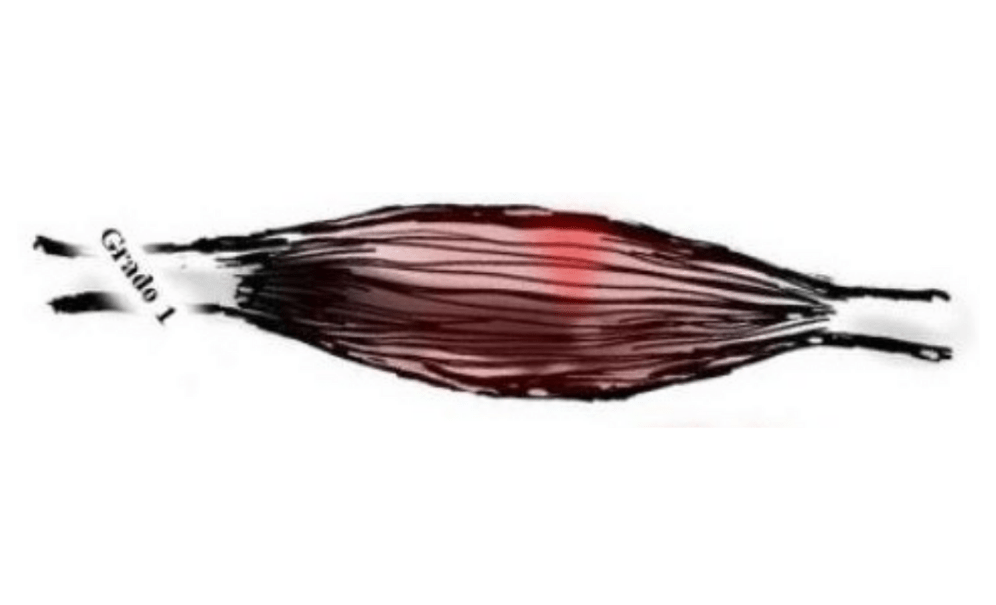

Grado I:

- Existe una ruptura mínima en las miofibrillas.

- Se puede percibir dolor que aumenta en realizar un movimiento.

- Se afecta ligeramente la movilidad y las actividades cotidianas.

- Hay un ligero aumento del volumen local( inflamación)

- Enrojecimiento (eritema)

- Aumento de la temperatura

Se puede iniciar el abordaje sin técnicas invasivas (cirugía) con un pronóstico favorable.

Pronostico de recuperación:

Variando dependiendo de la lesión recuperación de las capacidades de un 80 a 85% en el primer mes y medio-